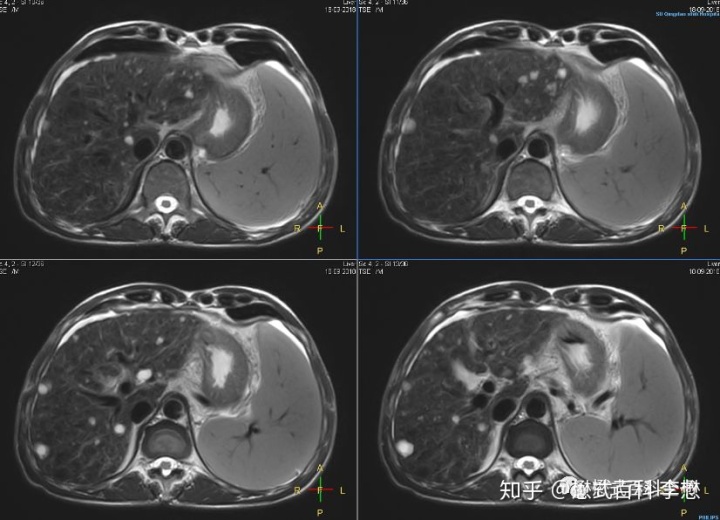

上图,各位临床医生一眼就能看出是腹部(肝脏)扫描的磁共振图。那么这个图到底是哪种加权像呢?是T1WI,还是T2WI,还是PDW?

我们通过一些简单的规律来判断,首先注意看胃里面,液体是高信号,在图中是亮的,所以这个图是T2WI图。